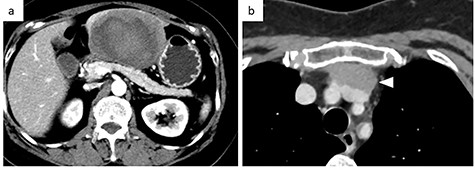

A 56-year-old woman presented to another hospital with acute abdomen. Computed tomography (CT) examination demonstrated a tumor 10 cm in diameter that protruded from the left lateral segment of the liver, with evidence suggestive of rupture of the liver tumor (Fig. 1). Since the patient was in good general condition, she was referred to our hospital for further evaluation. Her blood biochemical parameters when she was referred to our hospital were hemoglobin: 11.6 g/dl, albumin: 3.4 g/dl, γ-globulin: 18.5% and anti-acetylcholine receptor antibody: <0.3 nmol/L. Dynamic CT presented a liver tumor 10 cm in diameter, which was located at the left lateral segment of the liver, with a clear margin. A mass with an irregular margin was also identified in the anterior mediastinum (Fig. 2). On percutaneous angiography, since obvious extravasation of the contrast medium could not be identified, the arteries of the left lateral segment were embolized to prevent re-bleeding. Although a definitive preoperative diagnosis could not be made using magnetic resonance imaging (MRI) (Fig. 3), fluorodeoxyglucose positron emission tomography (FDG) showed increased FDG uptake in both the hepatic and anterior mediastinal tumors (Fig. 4). Although the liver tumor was suspected to be metastasis secondary to a thymoma based on the clinical findings, percutaneous tumor biopsy was performed to confirm the pathological diagnosis. The biopsy suggested malignant T-cell lymphoma or metastatic thymoma. In order to prevent re-rupture of the hepatic tumor, to confirm the pathological diagnosis and to potentially achieve a curative resection, the patient underwent laparoscopic left lateral segmentectomy (Fig. 5). Although the tumor was found to be adherent to the stomach, blunt dissection was possible. In addition, no peritoneal dissemination was detected. The surgical duration was 212 min and estimated blood loss was 50 ml. The liver tumor was pathologically diagnosed as metastatic thymoma type AB (Fig. 6). The patient’s postoperative course was uneventful and she subsequently underwent radical thymectomy 3 months after the liver resection. The thymic tumor was pathologically diagnosed as thymoma type B2. Currently, 30 months after thymectomy, she remains free from tumor recurrence.

MRI. (a) T1-weighted image: low-intensity area suggestive of intratumor hemorrhage. (b) T2-weighted image: the tumor had heterogenous intensity.

In the present case, contrast-enhanced CT demonstrated two-layered enhancement of the liver tumor. Considering the gross findings of the liver tumor, the inner layer consisted of a hematoma, and the outer layer was formed by compression of the tumor into a crescent shape by the intratumor hematoma, as seen on MRI. Since thymomas, including those that metastasize to the liver are soft, they can rupture easily and can be easily compressed by intratumor hematoma.